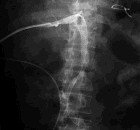

1.放射性監測是最有價值的診斷手段。某些放射性核素如60鑽、137銫、239鈽、90鍶等可通過體外測量的方法,作體內污染的檢測。分析排泄物和其它生物樣品中的放射性核素,也可用來估計體內含量,如測尿中鈾、釷、氚;測定糞中鐳、鍶;測定呼出氣中氡的含量,估算其母體核素在體內的含量;測定毛髮中的210PO估算體內鐳含量等,均是經濟、簡便而實用的檢測方法。2.針對放射性核素在體內選擇性蓄積的部位及器官,作相應的功能檢查。如親骨性核素作骨髓檢查和X射線骨骼攝片,親腎性核素作腎功能檢查。